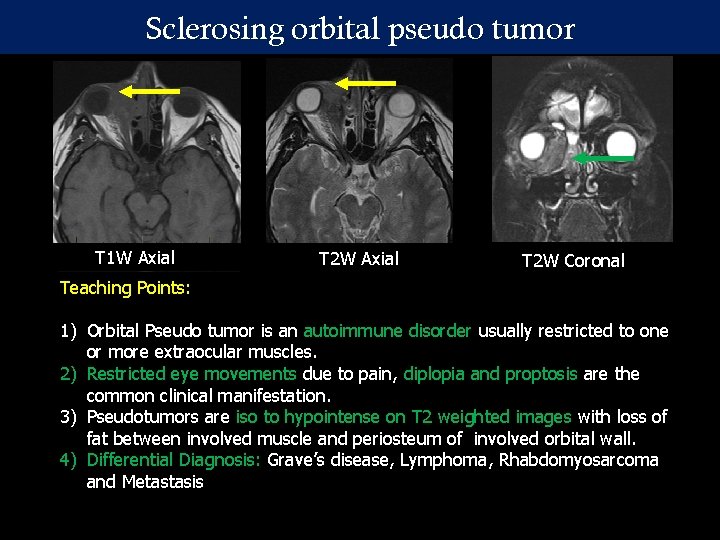

Sclerosing orbital pseudo tumor T 1 W Axial Teaching Points: T 2 W Axial T 2 W Coronal MRI of the orbit in 37 year old female : Homogenously enhancing 1) Orbital Pseudo tumor is an autoimmune disorder usually restricted to one soft tissue mass lesion in the or more extraocular muscles. medial canthus of the right orbit 2) Restricted eye movements due to pain, diplopia and proptosis are the with expansion of the nasolacrimal common clinical manifestation. duct, extending into the nasal 3) Pseudotumors are iso to hypointense on T 2 weighted images with loss of cavity with obliterating of the fat between involved muscle and periosteum of involved orbital wall. right osteomeatal complex. 4) Differential Diagnosis: Grave’s disease, Lymphoma, Rhabdomyosarcoma Extension also noted into the intra and Metastasis conal compartment of the orbit T 1 W Axial +C T 1 W Coronal + C with thickening of the medial and inferior rectus muscle.